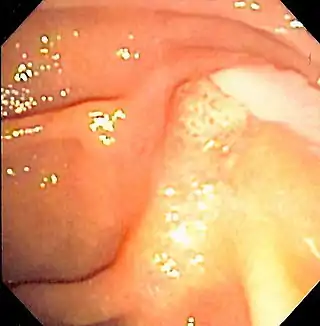

![]() Duodenoscopía que muestra la salida de pus de la ampolla de Vater, un hallazgo clínico de Colangitis. | ||